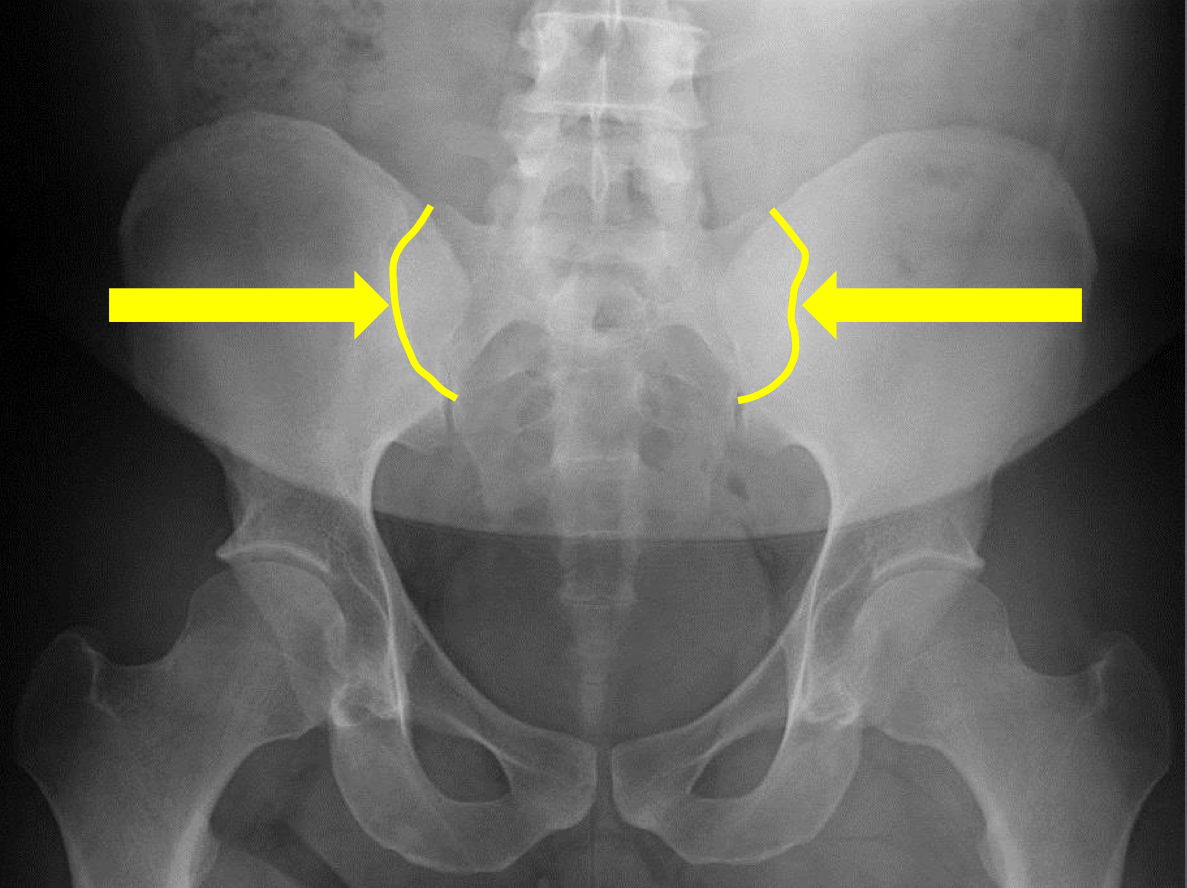

What view is this?

AP (Anterior to Posterior) LumboPelvic

What is this?

Femur Heads

What is this?

Superior Iliac Crests

What is this?

Lateral Iliac Crests

What is this?

Ischial Tuberosites

What is this?

Obturator Foramen

What is this?

S2 Tubercle

What is this?

Pubic Symphysis

What is this?

Sacral Groove

What is this?

Lateral aspect of sacrum

What is this?

Medial Aspect of Ilium